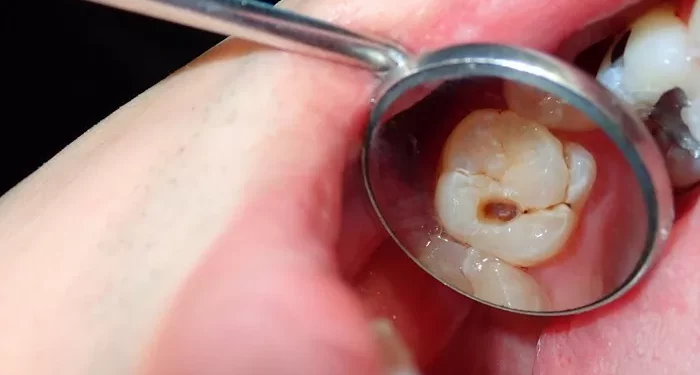

The Adult Oral Health Survey 2023, published on 9 December, found more than one in five adults in England have at least one tooth with obvious decay. When teeth with non-cavitated decay extending into the inner dentine are included, the share rises to 41% of dentate adults.

The report says the prevalence of obvious decay fell markedly between 1998 and 2009 but has since climbed. Between 2009 and 2023 the rate increased by 13%, a shift the authors call “almost a reversal of the previous improvement,” bringing 2023 figures closer to 1998 levels.